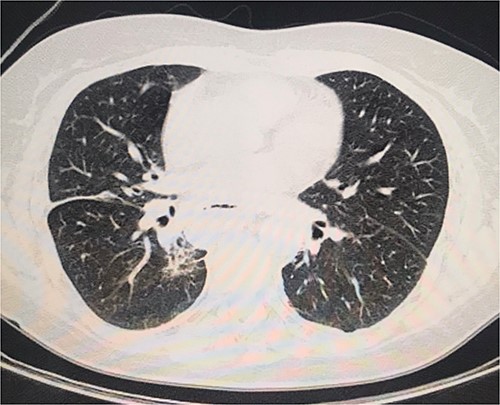

The abdominal computed tomography (CT) scan exhibited signs of esophagectomy with gastric lifting, a type IV hiatal hernia and colon herniation into the thorax (Fig. 1a and b). This was full of feces and symptoms of volvulus in the involved segment, with no free liquid in the cavity. Laboratory testing revealed an elevated protein C-reactive of 77, with normal white blood cells. Renal function and electrolytes were within normal limits.

Different sections of the CT study demonstrate the mediastinal position of the transversal volvulus. (a) Axial CT section of the abdomen showing signs of esophagectomy with gastric lifting, a type IV hiatal hernia and colon herniation into the thorax. (b) The coronal CT section of colon herniation into the thorax. (c) The sagittal CT section of the thorax and the abdomen shows the posterior mediastinal position of the colon herniation into the thorax.

On the second day postoperatively, the patient presented with dyspnea and fatigue; a new chest CT evidenced a hydropneumothorax on the left (Fig. 3). Water-seal chest drainage was performed, with an adequate re-expansion despite the chronicity of the hernia and improvement in ventilatory parameters and symptoms (Fig. 4). She was discharged after 9 days of hospitalization. Currently, she is doing well with a satisfactory response to treatment.

Second day follow-up showed a hydropneumothorax on the left chest CT scan.